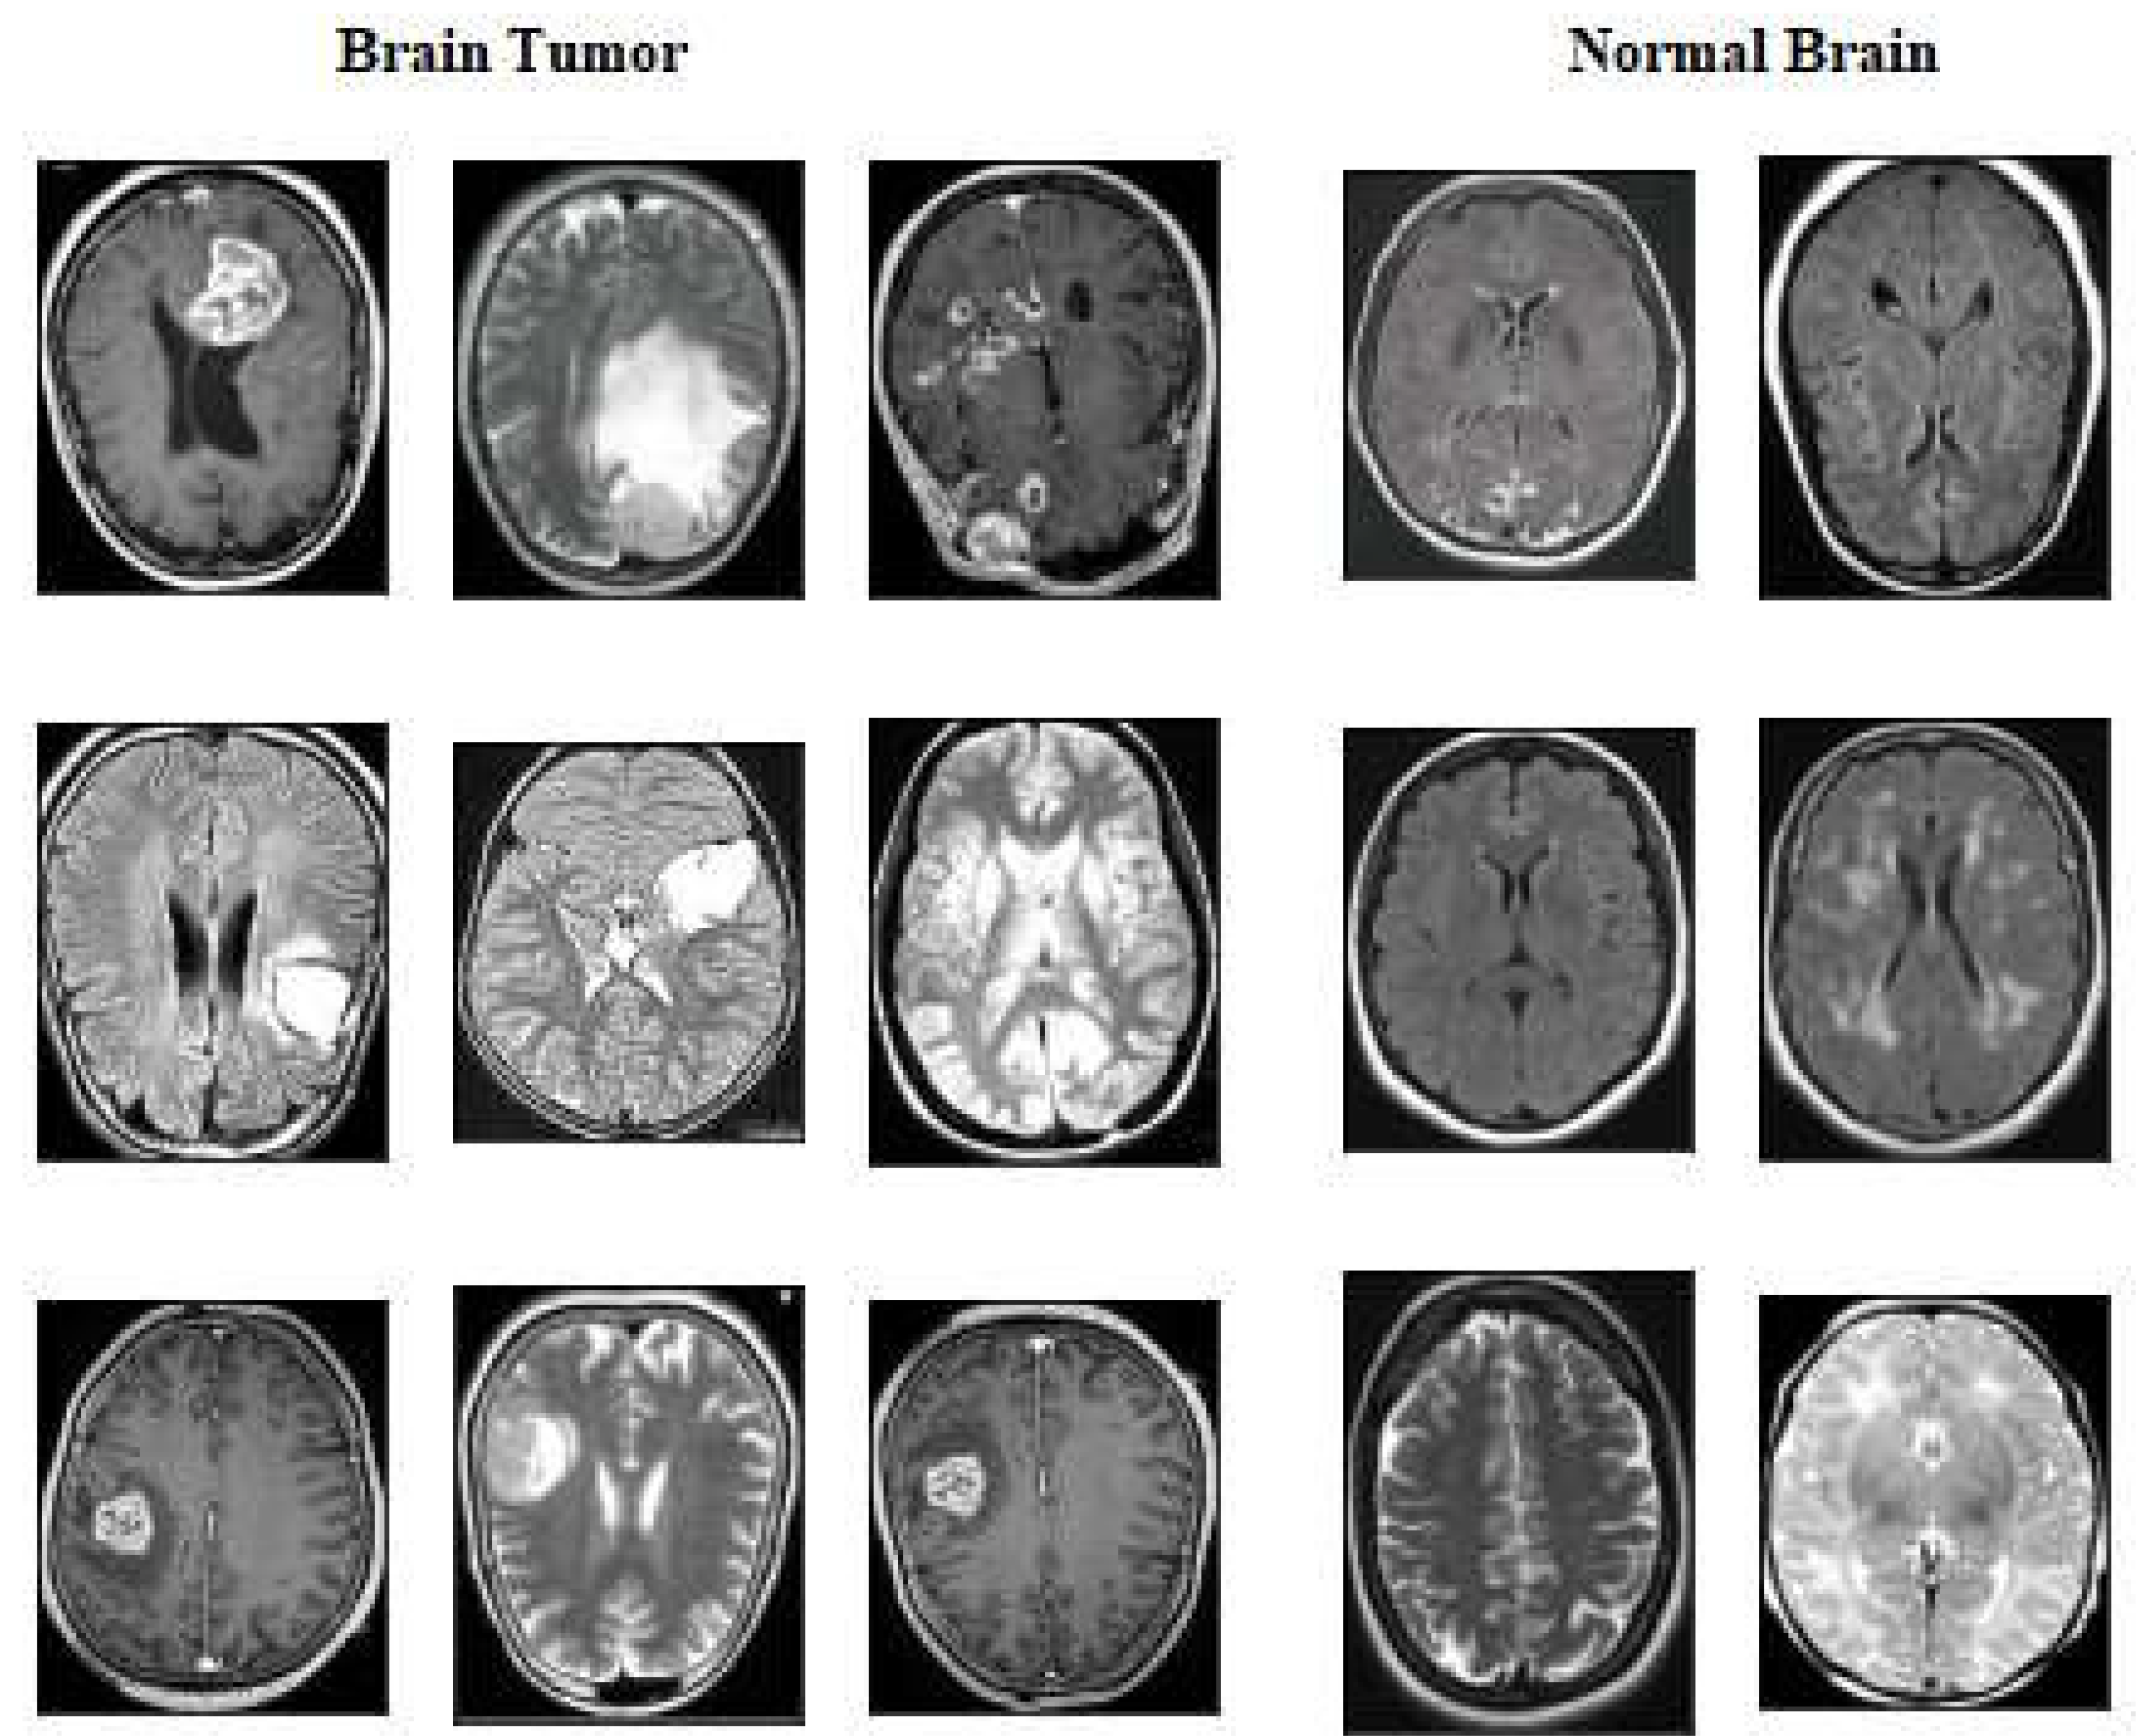

4.2. Dataset

| 2 | kaggle.com/datasets/ahmedhamada0/brain-tumour-detection |